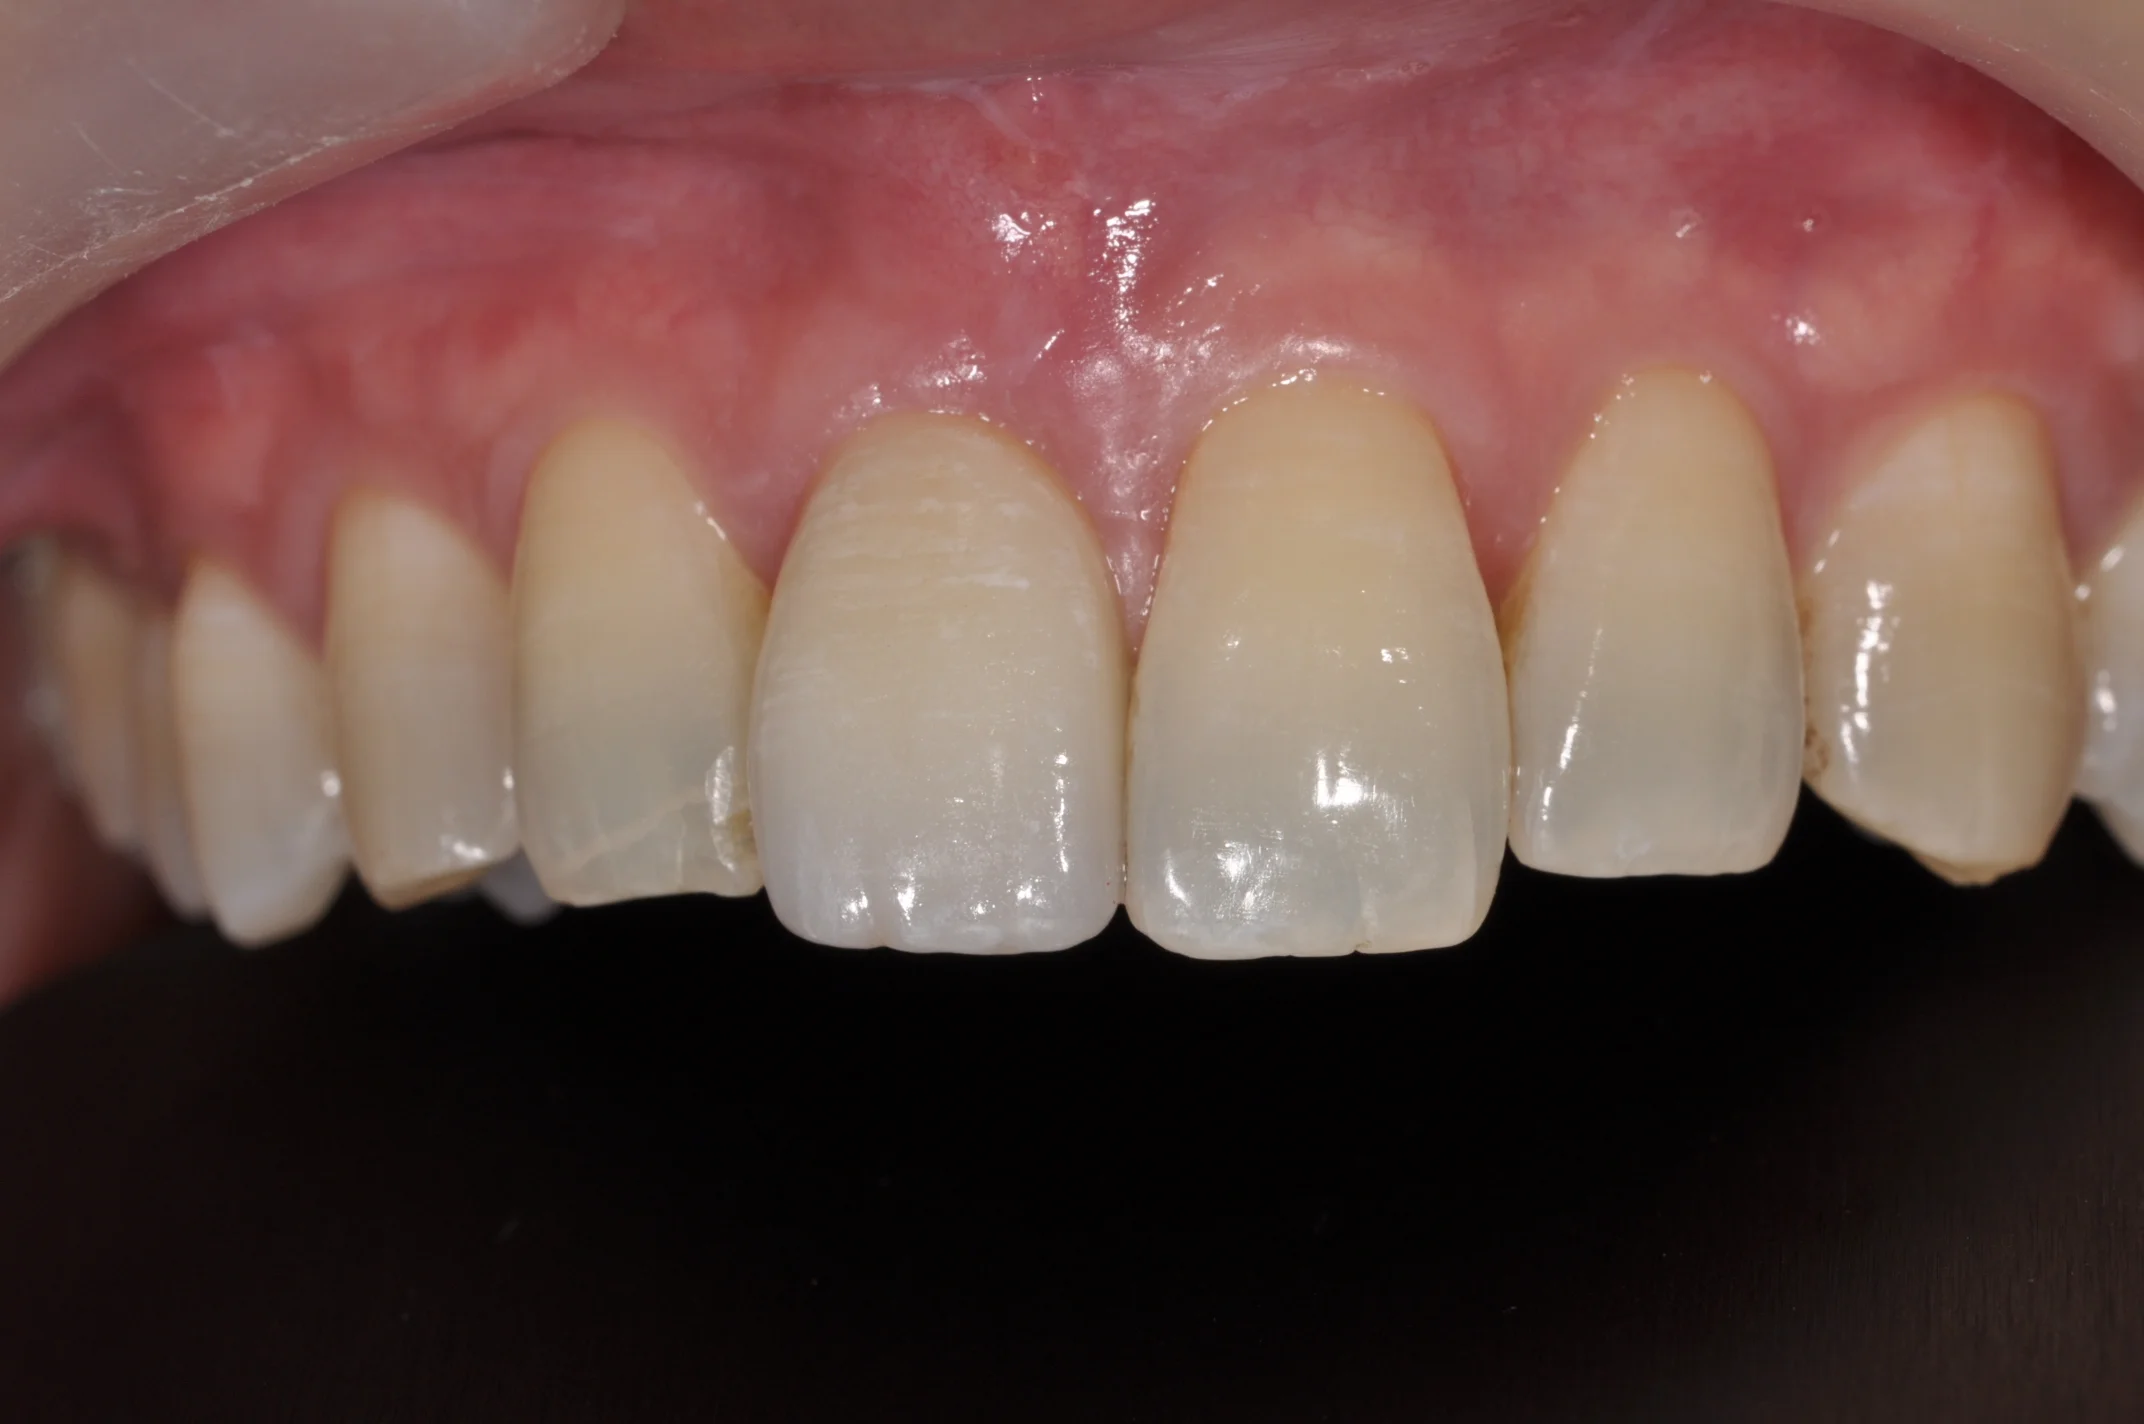

DSC_1041.JPG

DSC_1011.JPG

BEFORE

SINGLE FRONT TOOTH IMPLANT